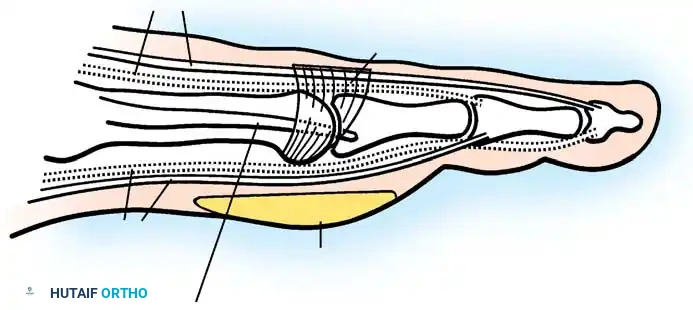

1. Approach: A dorsal longitudinal incision is made medial to the EHL tendon, extending from the mid-shaft of the first metatarsal to the interphalangeal joint.

2. Joint Preparation: The capsule is incised, and the collateral ligaments are released. The severely eroded articular surfaces of the first metatarsal head and the base of the proximal phalanx are resected. Cup-and-cone reamers are highly recommended to preserve length while allowing multi-planar adjustment.

3. Positioning: The hallux is positioned in 10 to 15 degrees of valgus and 15 to 20 degrees of dorsiflexion relative to the first metatarsal shaft. Neutral rotation must be confirmed to ensure the toenail faces directly dorsal.

4. Fixation: Rigid internal fixation is achieved using a dorsal contoured titanium plate and a lag screw across the arthrodesis site.

- Resection: The extensor tendons are retracted or lengthened (Z-plasty). The dorsal capsule is opened, and the collateral ligaments are sharply divided to allow plantarflexion of the metatarsal.

- Osteotomy: An oscillating saw is used to resect the metatarsal heads at the anatomical neck. It is imperative to create a smooth, parabolic cascade (the 2nd metatarsal should be the longest, tapering down to the 5th).

- Soft Tissue Balancing: The plantar plate and fat pad, which have migrated distally, are mobilized and pulled proximally under the remaining metatarsal stumps. If the toes remain contracted, closed osteoclasis or PIP joint resection arthroplasties may be performed.

- Pinning: Smooth Kirschner wires (K-wires) are driven antegrade through the toes and retrograde into the metatarsal shafts to hold the toes in neutral alignment.